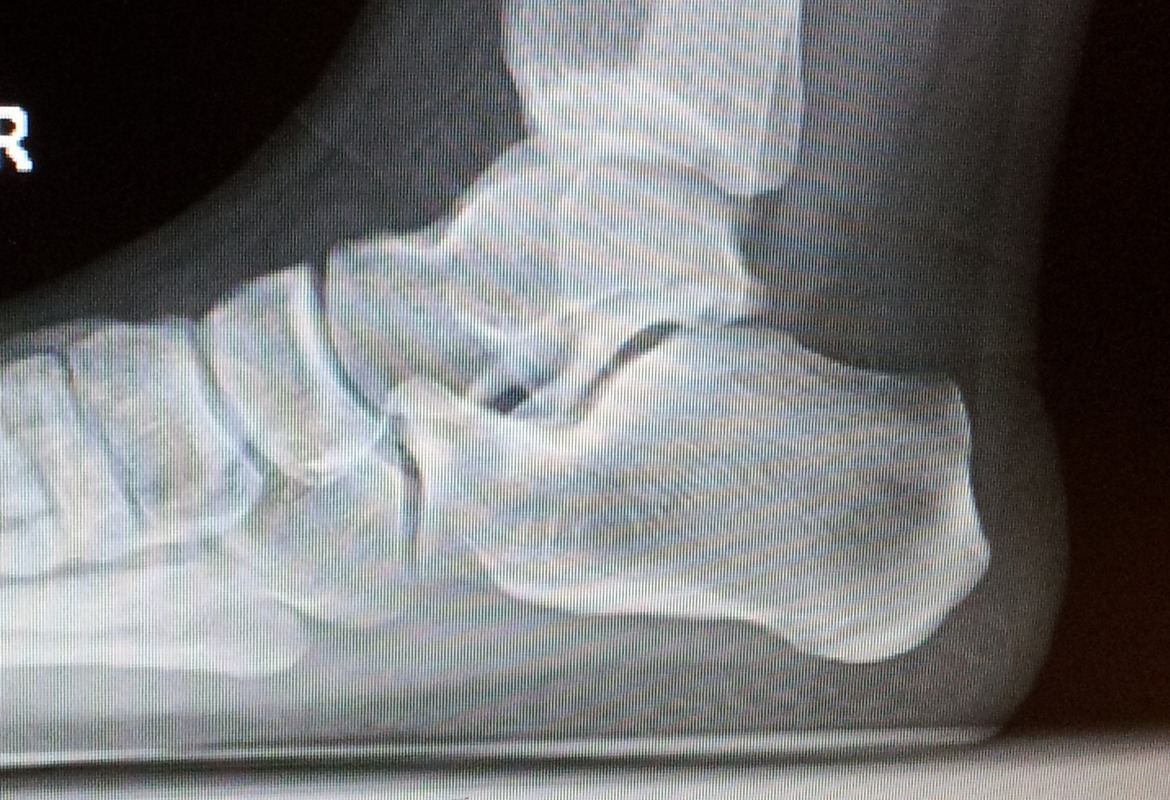

Calcificación calcánea posterior.

Si nos ceñimos a la patología descrita en sí, es decir, calcificación en el talón, esta calcificación puede estar localizada en la región plantar del pie (y comúnmente llamarse espolón calcáneo), o en la región posterior del talón (lo que en terminología médica se conoce como Haglund). En caso de que sea la primera de las cosas, que se diagnostica mediante una placa radiográfica (RX) en visión lateral (LAT) en carga y sin corrección, no es necesario hacer ningún tratamiento, pues el espolón calcáneo NO es causa de dolor, puesto que existe mucho tejido plantar entre el suelo y dicho espolón, que además crece longitudinal hacia delante, y no hacia plantar, y por tanto no se puede "clavar" contra nada.

Si estos pacientes tienen dolor en el talón, aunque en la RX aparezca dicha calcificación, el dolor habrá que averiguar de donde procede, pues como se ha comentado en la introducción de este artículo, hay hasta 10 patologías que dan dolor en el talón. En caso de que la calcificación esté por detrás del talón, ello también puede ser diagnosticado mediante una RX LAT en carga y sin corrección. Se apreciará un exceso de hueso colindando con el tendón de Aquiles. Este tipo de pacientes suelen presentar rojez o irritación en la piel de la zona, y el roce con el zapato ya les causa dolor. La fricción de tres objetos duros entre sí, esto es, el tendón de Aquiles, el reborde óseo del calcáneo prominente y el contrafuerte del zapato, hacen la situación perfecta para que se desarrolle el Haglund.